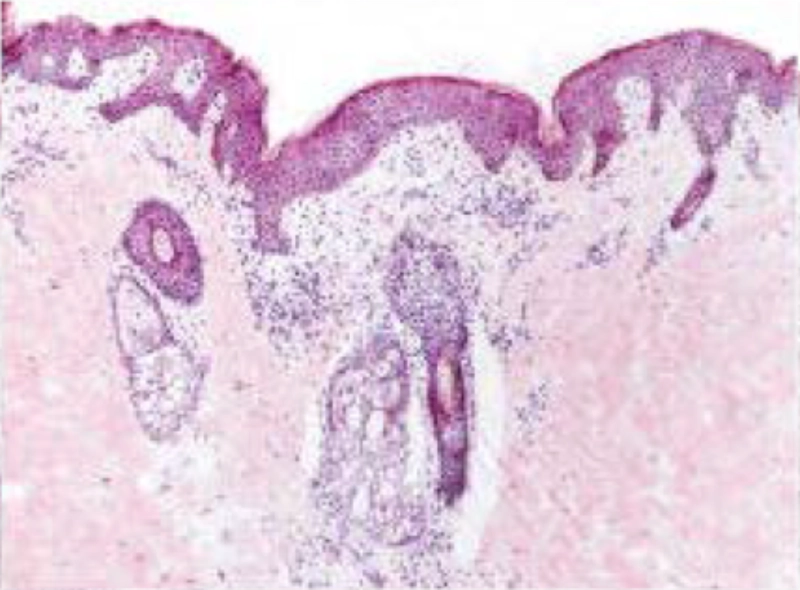

La piel sin lesiones no es una piel normal

En la dermatitis atópica, también se observa inflamación subclínica en la piel aparentemente sin lesiones

PIEL NORMAL

PIEL “SIN LESIONES”

En la dermatitis atópica crónica, la inflamación subclínica siempre está presente, incluso en la piel sin lesiones o de aspecto normal